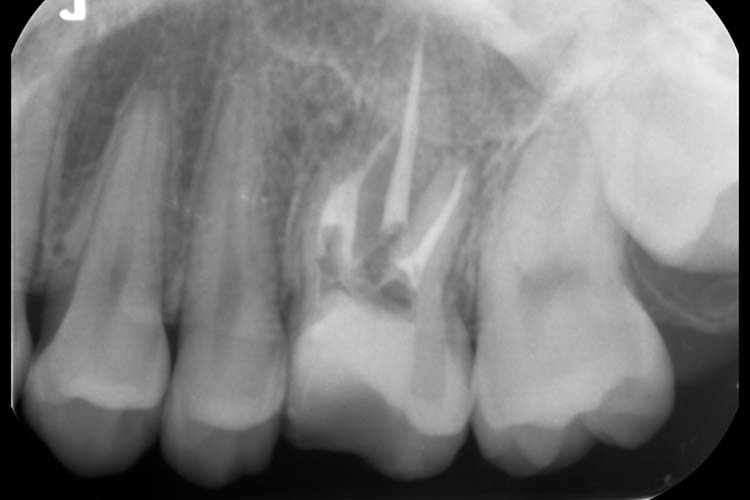

症例2

BEFORE

AFTER

| 主訴 | 左下の歯茎が腫れていて、何もしなくても歯が痛い。 |

|---|---|

| 治療期間 | 4回 約1ヶ月半 |

| 治療費 | 保険診療 |

| 治療内容 | 感染根管処置(根管治療) |

| 治療のリスク | 根管治療後、一時的に歯の根に痛みや違和感が生じることがあります。 |